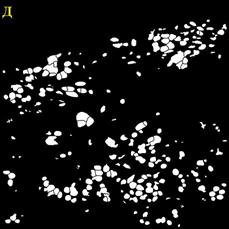

В ходе работы выполнен анализ трех изображений, с площадью покрытия клетками окна среза 80%; и 40%, а также наличия размытых границ клеток (Рисунок 3).

Рисунок

3 – Примеры обрабатываемых изображений. А – площадь покрытия клетками окна среза 80%; Б – площадь покрытия клетками окна среза 40%; В – наличия размытых границ клеток. Далее – изображения 1, 2, 3, соответственно

Для сравнения качества сегментации использовались маски ядер и клеток. Маски, полученные при помощи разработанного алгоритма, показаны на Рисунок 4.

4 – Результаты обработки изображений А – маска ядер изображения 1; Б – маска клеток изображения 1; В – маска клеток изображения 2; Г – маска клеток изображения 2; Д – маска ядер изображения 3; Е – маска клеток изображения 3

Разработанные алгоритмы показали хорошее качество сегментации для изображений с большим и малым количеством клеток. Однако алгоритм сегментации требует доработки при работе с нечёткими изображениями. В этом случае маска клеток содержит искаженные границы клеток для большинства ядер.

Количество клеток на первом изображении составляет 848, на втором 229, на третьем 218. Количество пропущенных либо раздробленных ядер и клеток не превышает 5% от общего числа клеток.